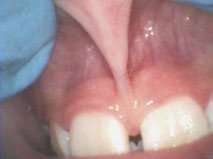

For example, Figures 2 shows the use of LightScalpel LS-1005 CO2 laser (2 watts SuperPulse Repeat Mode with F1-6 through F1-8 settings) for soft-tissue crown lengthening of the maxillary incisors and for labial frenum revision. Both procedures were performed during the same visit while the patient received local anesthesia. No sutures were placed. Figure 2 presents the self-correction of a rotated tooth #9 after the frenum revision. Laser frenectomies in Figure 3 resulted in spontaneous closure of midline diastemas.